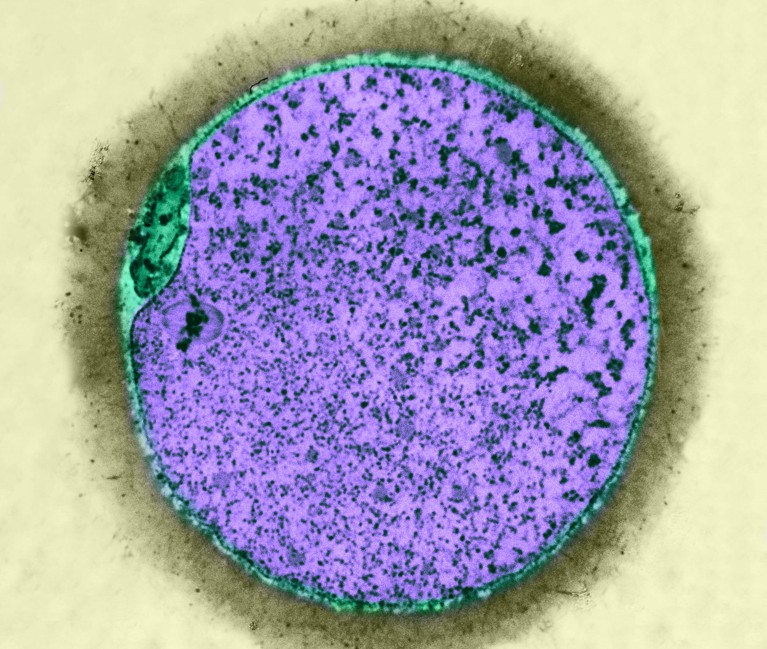

Las cosas han ido evolucionando en prevención, sabemos que la infección por el virus papiloma humano (HPV), es una condición necesaria para que se desarrolle el cáncer más frecuente del cuello del útero, la detección del DNA del virus se ha recomendado como herramienta de cribado en la población sana.

La limitación del uso de la detección del DNA viral del HPV como herramienta de cribado en la población sana, radica en que es un virus muy prevalente, la mayoría de la población ha estado en contacto con él y sólo una pequeña parte de las que dan positivas para la infección por el virus, desarrollarán un cáncer lustros o décadas después de identificada la infección.

Hay una forma de saber quiénes de las que dan positivas para el ADN del virus, tienen riesgo de desarrollar cáncer. En éstas el virus hace que se produzcan unas proteínas en las células, (E6/E7) que inhiben los genes que controlan el crecimiento celular, (el cáncer no es más que un crecimiento celular desordenado).

El ARN mensajero (RNAm), que codifica éstas proteínas, E6/E7, puede ser detectado en una muestra, de cérvix y vagina, de ésta forma se, podría saber, quiénes de las que dan positivas al virus, tienen riesgo de desarrollar un cáncer, en las décadas siguientes y quienes no.